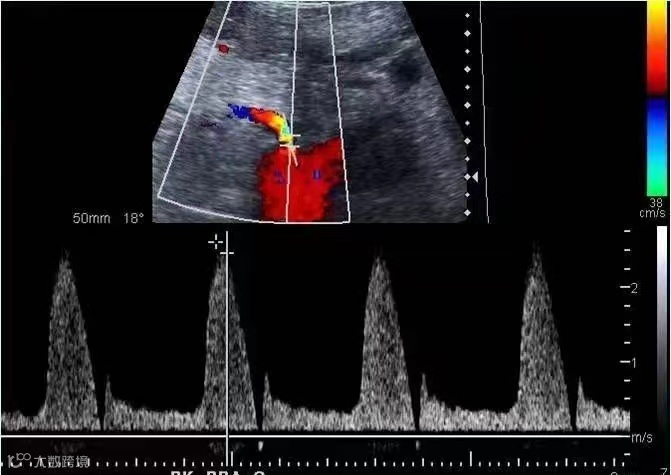

其实肾动脉狭窄是一种可治愈的疾病,手术缓解了狭窄后,肾脏血流动力学改善,不仅能纠正高血压,而且能保护受损的肾功能。因此,早期诊断与治疗就显得尤为重要。

综上,高血压患者检查肾动脉是十分必要的,超声作为首选筛查的检查方法具有明显的优势。